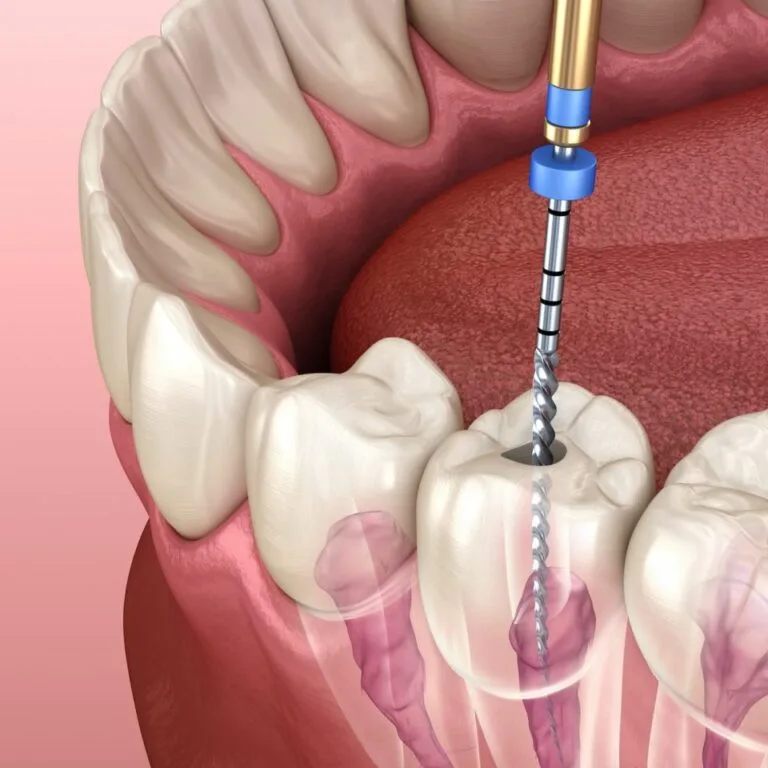

¿Qué es una endodoncia y cuándo la necesito?

Síntomas, procedimiento y recuperación. Conoce cuándo consultar a tu odontólogo…

Más información Agendar por WhatsAppConservación de piezas

Tratamiento de conductos para salvar piezas dentales afectadas por caries profundas o infecciones.

Síntomas, procedimiento y recuperación. Conoce cuándo consultar a tu odontólogo…